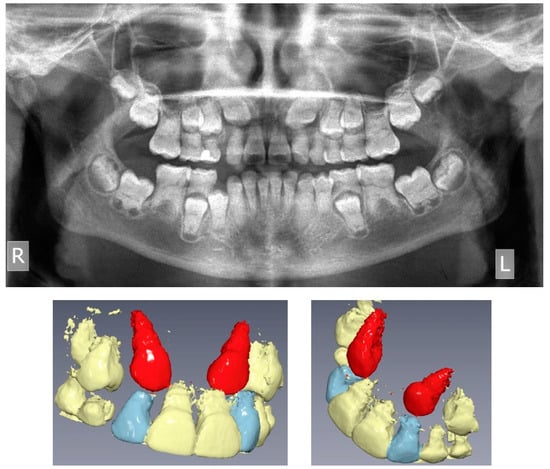

The pre-treatment panoramic radiograph revealed short root length of most of the teeth, delayed tooth eruption, obliteration of pulp chambers and periapical radio-lucencies, not associated with periodontal disease or pulp inflammation. Horizontal crescent-shaped lines along the cementoenamel junction were evident in several teeth. Based on radiographic characteristics, this patient was subclassified as DD-Ic [10]. The permanent maxillary canines were impacted (Figure 1). Pre-treatment cone-beam-computed-tomography scans showed that the upper right maxillary canine (#13) was labially impacted; the contralateral canine (#23) displayed a more palatal position. Both teeth were above the roots of the adjacent lateral incisors, in close proximity to them and to the roots of the central incisors (Figure 2). Sclerosis of the maxilla and the mandible was absent in this case, as well as in the skeleton (Figure 3).

Figure 3. Hand-wrist and long bone radiographic presentation of the daughter exhibiting no osseous defects.